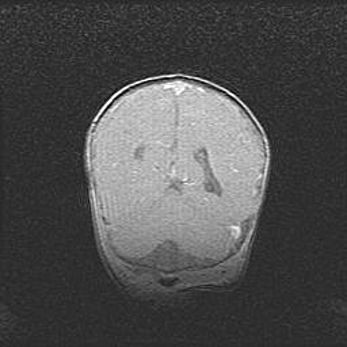

Открытая гидроцефалия.

Возраст: 9 месяцев 12 дней

Вес: 6800 г

Пол: мужской

Окружность головы: 41,5 см

Срок гестации: 28 недель

Гидроцефалия головного мозга у новорожденных имеет характерный признак: опережающий рост окружности головы приводит к визуально хорошо определяемой гидроцефальной форме сильно увеличенного в объёме черепа. Детские неврологи определяют следующие симптомы гидроцефалии у грудничков: выбухающий напряжённый родничок, частое запрокидывание головы, смещение глазных яблок к низу.